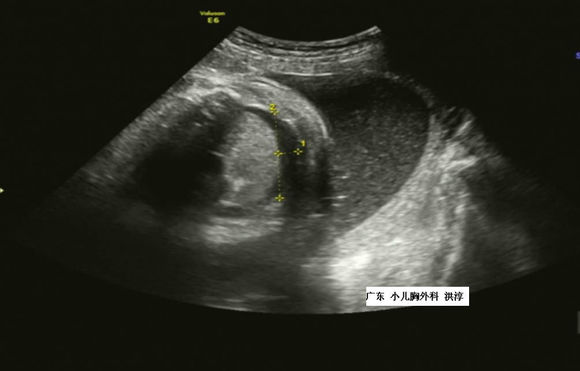

1.产前超声:产前诊断FHT主要依靠超声检查,超声表现为胎儿胸腔内心肺之间片状无回声区。单侧大量胸腔积液可有占位效应,出现心脏及纵膈移位,肺脏常被压缩变小。继发于胎儿水肿的胸腔积液,多为双侧性,双侧胸腔积液时表现为“蝙蝠翅膀”声像图。